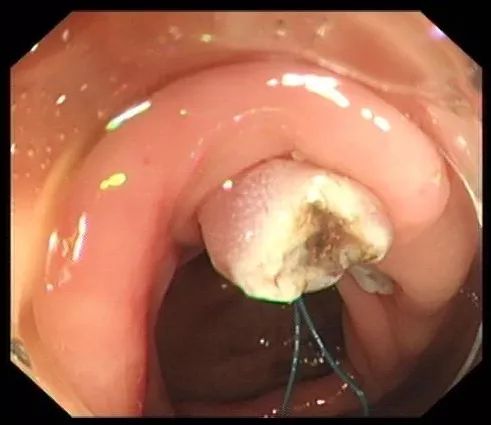

步骤三:将钢丝圈套住息肉,并于息肉根部收紧钢丝圈。

图片

步骤四:轻轻向肠腔内提起息肉,使钢丝圈尽量远离肠壁黏膜。

步骤五:在钢丝圈上脉冲式通高频电进行电灼烧,直至息肉根部被切断,息肉脱落。